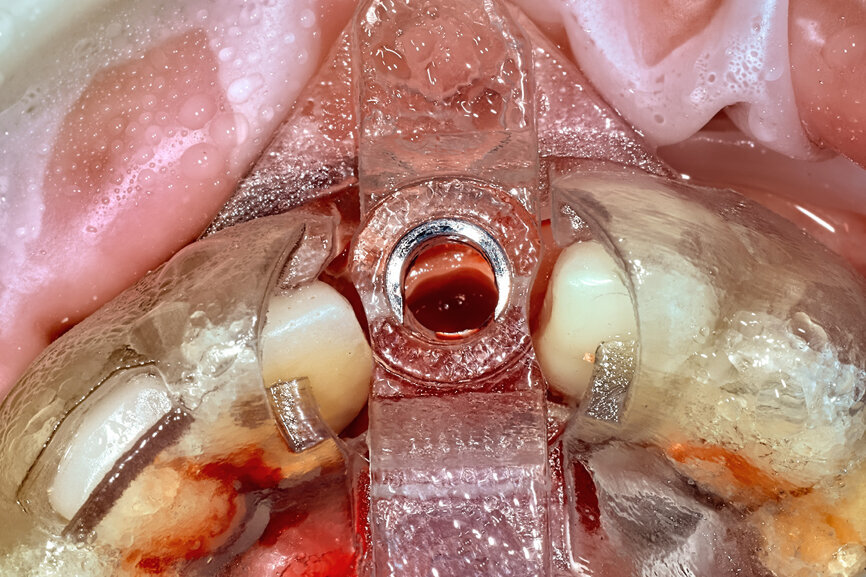

Fig. 22a: The final insert was designed to receive the guided sleeveless drills for accurate osteotomy preparation (a). The osteotomy was prepared to avoid

proximity to the remaining root fragment while leaving sufficient restorative space as previously planned (b).

Fig. 22b: The final insert was designed to receive the guided sleeveless drills for accurate osteotomy preparation (a). The osteotomy was prepared to avoid

Prior to the guided drilling, a Gates–Glidden drill was used to remove any gutta-percha within the root. Utilising the tooth-borne template and the first insert, initial long shaper drills (IS1, IS2) were used to reach the apex of the root (Root Membrane Kit; Fig. 17). A periapical radiograph confirmed that the apex length had been reached and that all the gutta-percha had been removed (Fig. 18). The second insert had a metal cylinder that allowed for the long, round diamond drills to shape the root into the desired crescent shape (Fig. 19a). The insert was removed to access the palatal root (Fig. 19b). Using appropriate instrumentation such as periotomes, elvatomes or FRINGS forceps (both TBS Dental), the palatal root was carefully removed (Fig. 20). A periapical radiograph confirmed that the palatal root had been completely removed (Fig. 21). The next insert contained the final diameter to receive the guided sleeveless drills for osteotomy preparation (Fig. 22a). The osteotomy was prepared to avoid proximity to the remaining root fragment while leaving sufficient restorative space, as previously planned in the software simulation (Fig. 22b). Implant placement (AnyRidge, MegaGen) was facilitated by the R2GATE surgical carrier for full-template guidance at the appropriate torque values (Fig. 23). Depth control and rotational positioning were accurately confirmed with the notch indicated on the template to correspond with the insertion tool (Fig. 24).